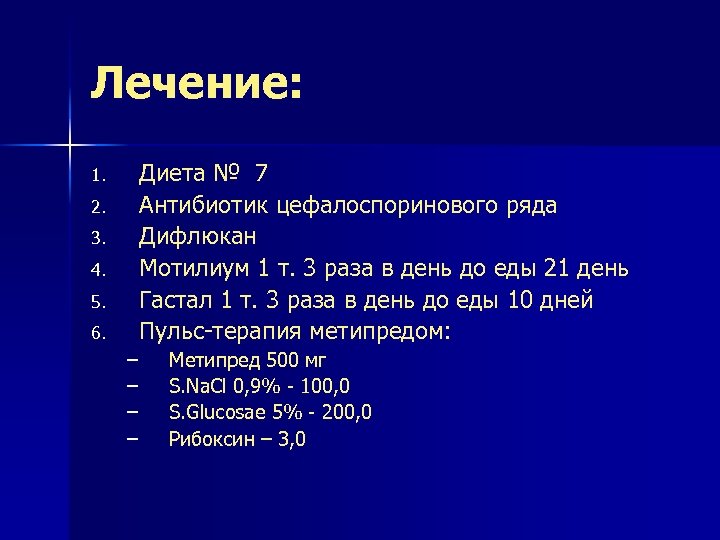

Лечение: 1. 2. 3. 4. 5. 6. Диета № 7 Антибиотик цефалоспоринового ряда Дифлюкан Мотилиум 1 т. 3 раза в день до еды 21 день Гастал 1 т. 3 раза в день до еды 10 дней Пульс-терапия метипредом: – – Метипред 500 мг S. Na. Cl 0, 9% - 100, 0 S. Glucosae 5% - 200, 0 Рибоксин – 3, 0

Лечение: 1. 2. 3. 4. 5. 6. Диета № 7 Антибиотик цефалоспоринового ряда Дифлюкан Мотилиум 1 т. 3 раза в день до еды 21 день Гастал 1 т. 3 раза в день до еды 10 дней Пульс-терапия метипредом: – – Метипред 500 мг S. Na. Cl 0, 9% - 100, 0 S. Glucosae 5% - 200, 0 Рибоксин – 3, 0